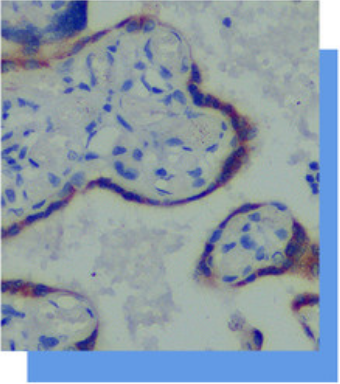

HCG是胎盘滋养细胞分泌的一种糖蛋白,

妊娠的绒毛滋养细胞染色阳性。 其主要应用于

绒毛膜上皮癌、葡萄胎(弱阳性)及恶性葡萄

胎(强阳性)的诊断;在生殖细胞肿瘤的胚胎

性癌、精原细胞瘤等可染色阳性。 在滋养细胞

肿瘤中其染色程度强及粗颗粒状,而其它上皮

性肿瘤中染色程度浅,细颗粒且均匀。